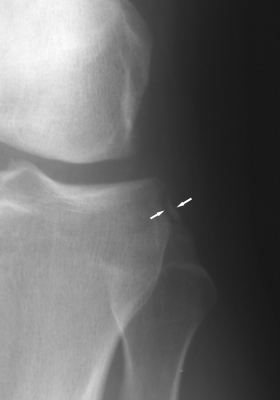

what is this finding called? association?

Segund fx

bony aculsion of anterolateral ligament

pathognominic for acl tear

associated with acl tear 75-100 percent of the time.